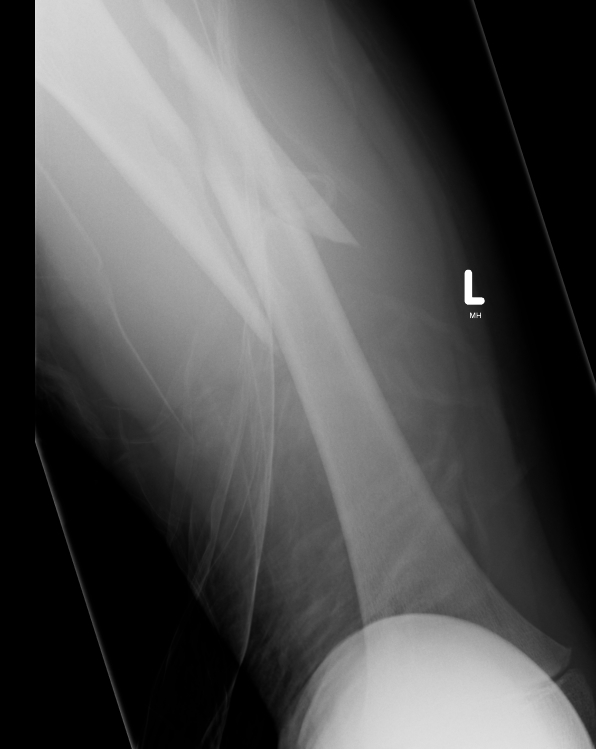

Flexible nails / Titantium Elastic Nails

Indications

- length stable i.e simple transverse, short oblique, midshaft

- maximum weight up to 50 kg / 12 years old

Contra-indications

- unstable fracture patterns

- > 50 kg

Technique

Wires

- 30 - 40% of diameter of diaphyseal medullary canal

- i.e. if canal 10 mm wide, use 2 x 4 mm

- 6 - 8 years (3 mm)

- 9 - 11 years (3.5 mm)

- 12 - 14 years (4 mm)

- recommend using 2 wires same diameter to avoid rotational instability

- 3 point bend in wires to get 3 point fixation

- aim for bend at fracture site

Entry points

- medial and lateral insertion

- 1 - 2 cm proximal to distal femoral physis

- oblique entry with awl in direction of nail insertion

- can open with drill bit

- beware proximity of the femoral artery medially

- entry points should be symmetrical

Wire passage

- bend wire for 3 point fixation

- also bend the tip of the wire

- can use F Tool to reduce fracture

- may need small incision and open reduction

- medial entry wire will pass into femoral neck

- lateral entry wire will pass into greater trochanter

- use designated TEN wire cutter to cut wires

- cut off, tap in slightly further, leave 1.5 cm out so can retrieve

- wires that are too prominent can cause bursa / limit flexion / pain / protrude through skin

Acceptable alignment

- 10o varus / valgus

- 15o flexion / extension

- 15 mm shortening